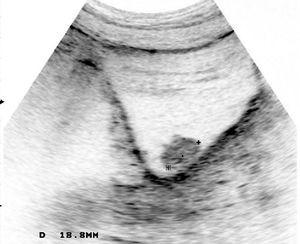

A su llegada a nuestro servicio se realiza analítica general y de marcadores tumorales, sin hallazgos patológicos. Se considera necesaria una ecografía renal y vesical (fig. 1) que muestra una lesión ocupante de espacio, exofítica, en la pared vesical derecha, de unos 4 cm de diámetro. La TC pélvica (fig. 2) confirma una masa parietal intravesical, aunque sin evidencia de afectación ganglionar perivesical ni retroperitoneal.

Figura 1. Ecografía vesical: lesión ocupante de espacio, exofítica, en la pared vesical derecha, de unos 4 cm de diámetro.